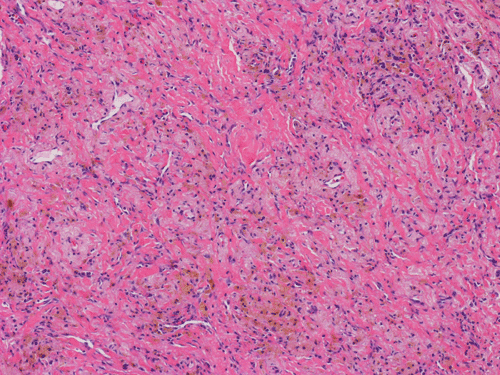

At scanning magnification (Panel A), the lung parenchyma is replaced by some coalescing fibrous nodules. The degree of involvement is variable at different fragments (Panel B and C). In the less affected areas, there are some fibrotic thickening of the septa (Panel C). In some areas, the changes are minimal and the pleural appear to be uninvolved (Panel D and E). In low to medium magnifications, these nodules of fibrosis contains a large number of hemosiderin laden macrophages (Panel F and G) admixed with fibrous tissue. The diagnostic tissue, however, is present in areas with increased cellularity. In these areas, there is a background of cells with a moderate amount of cytoplasm and bland nuclei. Some of these nuclei have kidney shape (arrow in Panel H). In some areas, many of the nuclei have a deep nuclear groove that resemble a coffee bean (arrow in Panel I). In the third type of areas, the nuclear grooving is not distinct (Panel J). Prominent eosinophilic infiltrations are almost always present. Immunohistochemistry on CD1a revealed many positive cells (Panel L). Also present in the specimen are multiple small blood vessels with thickened intima (Panel K). A Movat pentachrome stain demonstrates an internal elastic layer in these vessels and confirms that these are arteries (Panel M and N).

In the early stage of PLCH, there are interstitial infiltrates composed of LCs, lymphocytes, macrophages, eosinophils, plasma cells and fibroblasts 4. The infiltrates enlarge to form nodules centered on the small airways. Brown pigmented macrophages (smokers macrophages) are present in and around the nodules. Eosinophils tend to localize at the innermost layer of the nodules, where LCs can be most easily found in the thickened interstitium. Associated patchy interstitial and airspace organization or respiratory bronchiolitis may be present. Other smoking related changes are also common. Cavitation often occurs within the nodules which represents either an airway remenant or de novo cavitation as the inflammatory infiltrate enlarges. There is centripetal replacement of the nodules by fibroblasts which produce the classic stellate lesions of PLCH. As the disease progresses, the number of nodules, cavitary granulomas and fibrotic scars increase in number.

In the end stage, the exhausted lesions are predominantly fibrotic and largely depleted of LCs. In some regions, the fibrosis may surround cystic spaces of variable diameter to form large areas of honeycombing. This is especially predominant in the upper lobes. In cases where parenchymal scaring is present, the pulmonary function will be largely compromised. At this stage, both pulmonary function tests and radiologic findings may suggest diffuse lung disease, but biopsy will show stellate fibrotic lesions centered on the terminal airways with no identifiable interstitial inflammation. Pulmonary vasculopathy (in areas of lung remote from parenchymal nodules) is also seen in late stage PLCH. Vasculopathy manifests as intimal fibrosis, medial hypertrophy or luminal obliteration involving both venules and arteries. This may account for pulmonary hypertension seen late in PLCH.